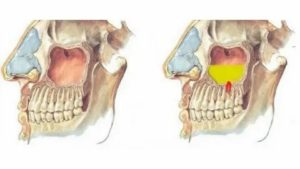

Посмотрите как это выглядит на схеме на примере гайморовых и лобных пазух.

Гайморовы пазухи (Г) имеют выводное соустье сверху, а лобные пазухи (Л) — снизу, это как бы перевернутые вверх дном бутылочки.

Эта схема, конечно же утрирована. В жизни все несколько сложнее…

Итак, как уже отмечено, верхнечелюстная пазуха находится около носа, поэтому она и называется – околоносовая (придаточная). На рисунке справа показано расположение всех придаточных пазух, в т.ч. и гайморовых. Как видно, располагаются последние сбоку от наружного носа. Вход в пазухи располагается в полости носа, на боковых ее стенках.

Этот процесс отражен на рисунке справа, где зелеными стрелками показан ток слизи из гайморовой пазухи в полость носа. С другой стороны само отверстие из гайморовой пазухи покрыто слизистой оболочкой, поэтому, в случае отека последней, отверстие резко суживается, что значительно затрудняет отток слизи.

Этот механизм хорошо отражен на рисунке справа. Видно, что слизистая гайморовой пазухи (ярко розовая) увеличена в объеме. Окружностью выделено отверстие из гайморовой пазухи в полость носа. Если сравнить это образование с предыдущим рисунком, то хорошо видно, что вследствие отека слизистой, соустье (мед.

термин, обозначающий отверстие) резко сужено и практически не имеет сообщения с полостью носа.